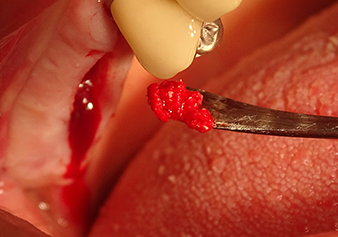

A periosteal elevator is used to place an augmentative mixture carefully into the region of the internal maxillary sinus ostium in the apical direction

Fig.8: A periosteal elevator is used to place an augmentative mixture carefully into the region of the internal maxillary sinus ostium in the apical direction.

Following an intermediate check (Fig. 4) a further preparation step was performed (Fig. 5). Afterwards, the hydraulic Z35P instrument was used to lift the membrane to the desired position (Fig. 6 and 7). This was followed by further piezosurgical preparation of the implant bed, concluded with a rotary bur and shoulder milling cutter up to the implant diameter of 4.8 mm. Before the implant was inserted, the augmentation material (particle size approx. 0.8-1.6 mm) was introduced underneath the Schneiderian membrane (Fig. 8).